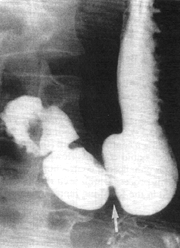

In all 120 cases a stage was awaited in which the duodenal cap was filled, in which the normal division between the stomach and duodenum (the pyloric ring) was clearly visible, and in which the pyloric region as well as the duodenal bulb were free of contractions, i.e. a motor quiescent phase (Fig. 11.1, 11.2). Measurements at this stage showed that the width of the normal indentation between the stomach and duodenum (the pyloric ring) on the lesser curvature, was more or less equal to the width on the greater curvature (Fig. 13.5) (see also Fig. 11.1 and 11.2). At this stage it is also seen that the pyloric aperture is patent, that it contains barium and that its diameter can be measured.

![]() |

| Fig. 13.5. Normal pyloric ring (arrow) in motor quiescent phase. Width of ring on lesser curvature more or less equal to that on greater curvature. Note patent pyloric aperture with diameter of 9 mm, containing barium |